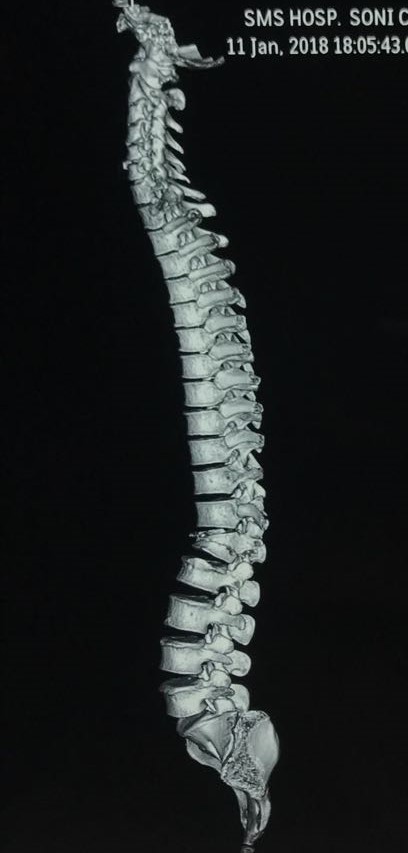

13 yrs female with cong kyphoscoliosis and d10 posterolateral wedge hemivetebra.

kyphosis 104 degree and scoliosis 43degrees.

Did vcr d10 with correction of deformity, fixation and fusion. Post op spine balnced in both sagittal and coronal planes.

Patient neurology intact. Mobilised.